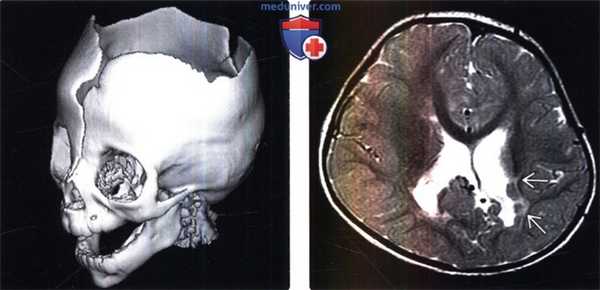

(Слева) КТ в костном режиме, сагиттальная косая 3D реконструкция: голова пациента с крупным дефектом свода черепа при синдроме амниотических перетяжек. Обратите внимание на отсутствие верхних отделов лобной и теменных костей. Наблюдаются «открытые» верхние отделы свода черепа.

(Справа) МРТ, Т2-ВИ, аксиальный срез: у этого же пациента с синдром амниотических перетяжек определяется потеря объема вещества левой теменной доли и неровность контуров эпендимы в сочетании с перивентрикулярной узловой гетеротопией серого вещества.